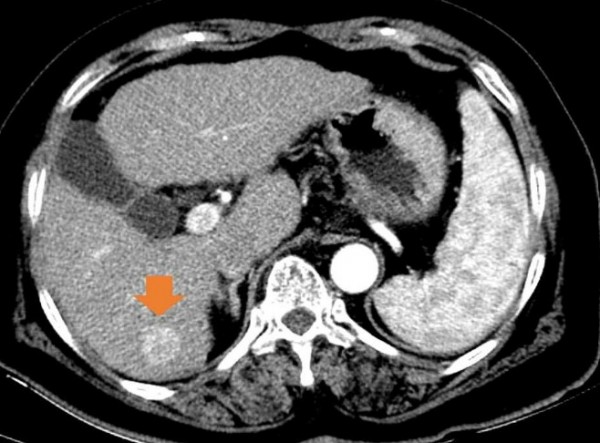

[오행생식 김미자 기자] 28일 국민건강보험공단이 건강보험 진료데이터를 활용해 2017년부터 2021년까지 간세포암(사진 1,2))’ 질환에 대해 분석한 결과 진료인원은 201759,040명에서 202164,525명으로 5,485(9.3%)이 증가하였고, 연평균 증가율은 2.2%로 나타났다.

사진1: 초기 간세포암, 사진 2:  진행된  간세포암 사진